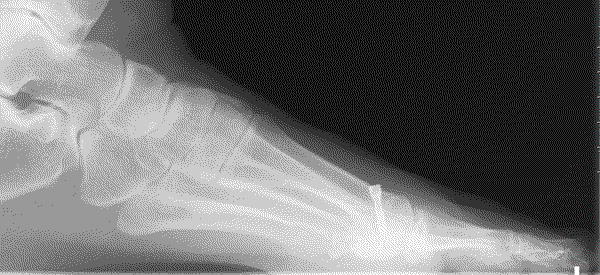

The severity of the condition is assessed by an X-ray. There is no direct correlation between the size of the deformity and the degree of symptoms experienced.

The aim of the surgery is to realign the first metatarsal almost parallel to the second metatarsal. This will move the big toe back into a straight position. This is achieved by cutting the bone. Sometimes re-balancing the soft tissue around the joint or taking a small wedge of bone out of the big toe is also required (Akin). The outcome of your operation will be dependent on the quality of your joint, the degree of arthritis present. There are numerous operations to correct bunions, but essentially, they fall into two categories: transposition and rotational procedures. Transposition osteotomies include the ‘Scarf’ and the ‘capital’. Rotational procedures include the ‘Lapidus’.

A transposition osteotomy such as a Scarf or capital osteotomy is where the bone is cut and moved across. The amount of correction available is restricted by the width of the bone. It is ideally suited to moderate deformities. In severe cases a rotational procedure such as a ‘Lapidus’ is preferred. Here a greater degree of correction is available. This operation also takes longer to heal and to settle down. Either procedure may be combined with an ‘Akin’ to help move the big toe to a straight position.